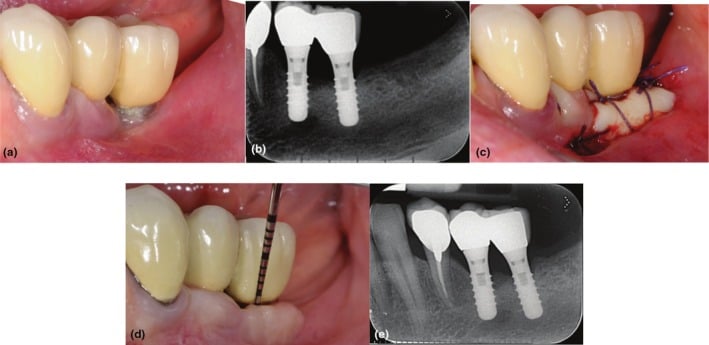

Clinical (a) and radiographic (b) views of the distal implant in region 3.6, placed 8 years earlier, demonstrate the lack of keratinized tissue (KT), peri‐implant soft‐tissue recession, and plaque accumulation. A free gingival graft (FGG) was performed to enhance the peri‐implant soft‐tissue conditions (c). Clinical (d) and radiographic (e) evaluations at the 20‐year follow‐up reveal minimal peri‐implant probing pocket depth, no bleeding on probing, and stable peri‐implant soft‐tissue conditions.